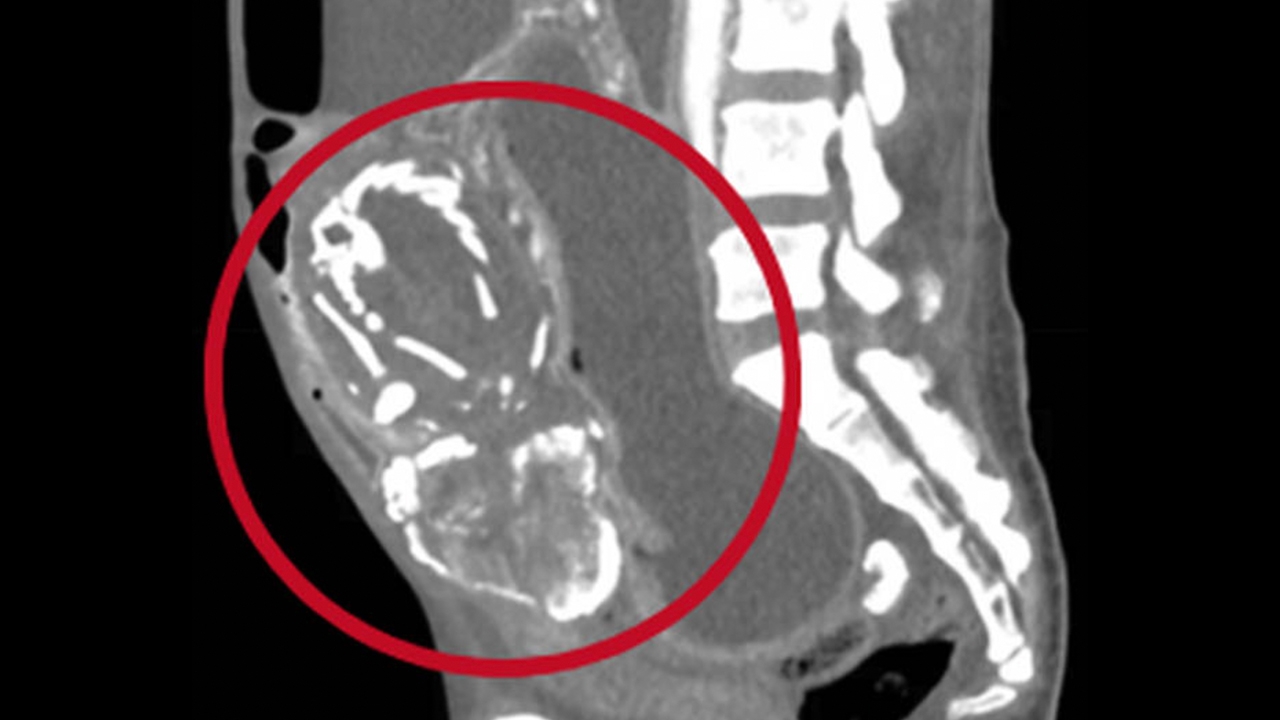

ตามรายงานระบุว่า หญิงวัย 50 ปีผู้นี้ ได้เกิดภาวะ 'ตั้งท้องนอกมดลูก' และได้เกิดการแท้งลูก ขณะตั้งครรภ์สัปดาห์ที่ 28 แต่ทารกไม่ได้หลุดออกมาจากร่างกายและได้กลายสภาพเป็น 'ทารกหิน' เพราะมีหินปูนหรือแคลเซียมมาเกาะ และอยู่ในท้องของหญิงผู้นี้มานานเกือบทศวรรษ

หญิงคนดังกล่าว ซึ่งมาจากประเทศคองโก และแพทย์ไม่เปิดเผยชื่อ ได้มาพบแพทย์ในนิวยอร์ก ด้วยอาการปวดท้อง อาหารไม่ย่อย และมีลมในท้อง หลังกินอาหารทุกมื้อ จึงทำให้แพทย์ทำการตรวจวินิจฉัยและสแกนท้องของเธอ จึงพบว่าคนไข้หญิงวัย 50 ปีรายนี้ มี 'ทารกเป็นหิน' อยู่ในท้อง และได้ไปกดทับการบีบตัวของลำไส้เล็ก จึงทำให้ร่างกายของเธอไม่ได้รับสารอาหารที่จะถูกดูดซึมเข้าสู่ร่างกาย

ดร. Waseem Sous กล่าวว่า หญิงคนนี้ ซึ่งมีลูกแล้ว 9 คนได้ยุติการตั้งครรภ์ในสัปดาห์ที่ 28 เนื่องจากเกิดภาวะท้องนอกมดลูกโดยทารกมีการพัฒนาเติบโตอยู่ในช่องท้อง แทนที่จะอยู่ในมดลูกของแม่ ทำให้ไม่มีเลือดเพียงพอที่จะส่งไปถึงลูก เป็นเหตุให้ทารกเสียชีวิต ในขณะที่ร่างกายของแม่ก็ไม่สามารถขับทารกที่ตายแล้วให้ออกมาได้ จึงก่อให้เกิดอาการป่วยที่ซับซ้อนจนทำให้แม่เสียชีวิต ซึ่งนับเป็นเคสที่เกิดขึ้นได้ยาก และมีสถิติมีผู้เสียชีวิตเพียง 290 รายเท่านั้น นับตั้งแต่มีผู้เสียชีวิตรายแรกในฝรั่งเศส ปีค.ศ. 1582

Cr ภาพ// Waseem Sous